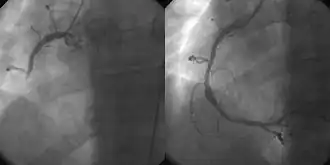

Die Gefäßdarstellung (Angiografie) der Herzkranzgefäße im Rahmen einer Herzkatheteruntersuchung erlaubt den direkten Nachweis von Verschlüssen und Verengungen. Sie wird entweder so früh wie möglich als Notfall-Untersuchung zur Vorbereitung einer PTCA (vgl. Reperfusionstherapie) oder im weiteren Verlauf bei Hinweisen auf fortbestehende Durchblutungsstörungen des Herzmuskels durchgeführt. Nachteilig kann die hohe Strahlenbelastung von bis zu 14,52 mSv sein. Das ist so viel wie bei 725 Röntgen-Thorax-Bildern.[51] Jedes Jahr werden weltweit mehrere Milliarden Bilder mittels der Strahlentechnik angefertigt – ungefähr ein Drittel dieser Aufnahmen bei Patienten mit akutem Myokardinfarkt. Zwischen den Jahren 1980 und 2006 ist die jährliche Dosis um schätzungsweise 700 % angestiegen.[52]